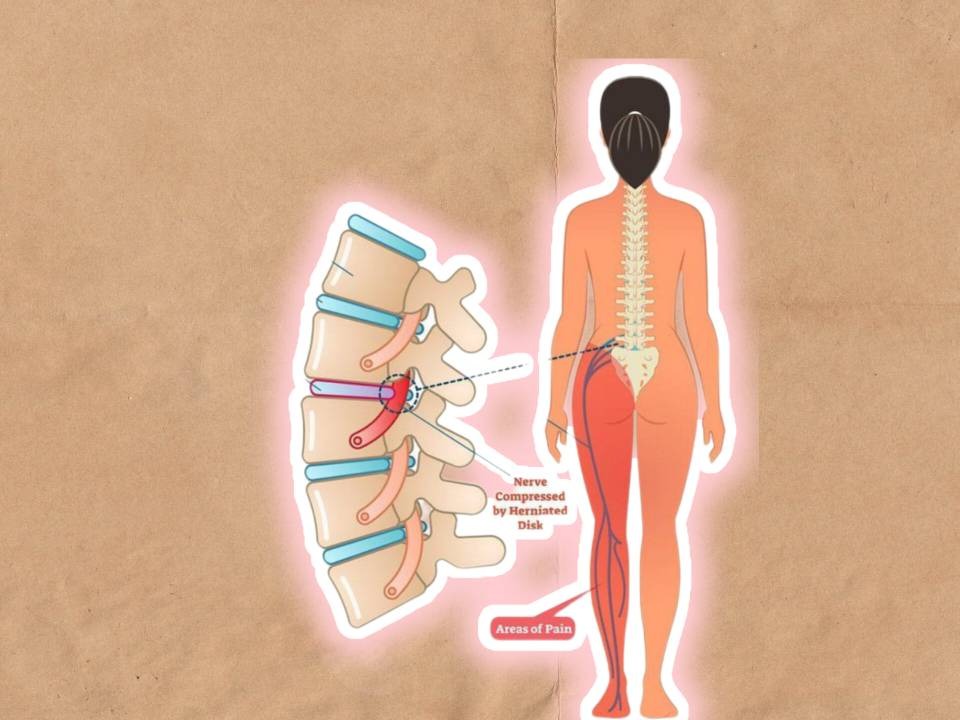

گیر افتادگی عصب سیاتیک می تواند منجر به درد کمری شود.

درد سیاتیک

از کمر شروع می شود و در باسن، پشت ران و ساق ادامه می یابد. معمولا به طور ناگهانی شروع می شود. در این ناحیه های گفته شده بی حسی و ضعف هم گزارش می شود.

عصب سیاتیک

بزرگ ترین عصب بدن است که از باسن و پشت پا می گذرد. این عصب در هر دو سمت، پای چپ و راست وجود دارد. هر گونه فشار بر روی این عصب منجر به درد در همه طول عصب می شود. درد سیاتیک بیشتر در سن 30 تا 50 سالگی گزارش می شود.

علت های درد سیاتیک

عوامل متفاوتی در درد سیاتیک وجود دارند که مهم ترین آن ها شامل:

1- پارگی دیسک: بیرون زدگی دیسک می تواند عصب سیاتیک را تحریک کند به طوری که منجر به درد و بی حسی شود. تا 5% کمر درد ها ناشی از بیرون زدگی دیسک اند.

2- تنگی کانال نخاعی: به جهت تنگی و باریکی بیش از اندازه کانال نخاعی فشار به نخاع وارد می شود.

3- لغزش مهره یا اسپوندیلولیستزیس: به رانده شدن یک مهره به سمت جلو بر روی مهره زیرین.

4- سندرم پیریفورمیس: اختلال در عضله پیریفورمیس به طوری که عضله سفت و منقبض می شود و عصب سیاتیک را تحریک می کند. این عضله در ناحبه باسن قرار دارد.

علائم درد سیاتیک

ضعف عضلانی، بی حسی، حس سوزش، درد، از دست دادن حرکت در پا ها، گزگز شدن یا سوزن سوزن شدن و بی اختیاری ادرار از مهم ترین علائم درد سیاتیک به شمار می آیند.

درد سیاتیک یکی از دلایل شایع کمر درد و درد در پا ها است.

تشخیص و درمان درد سیاتیک